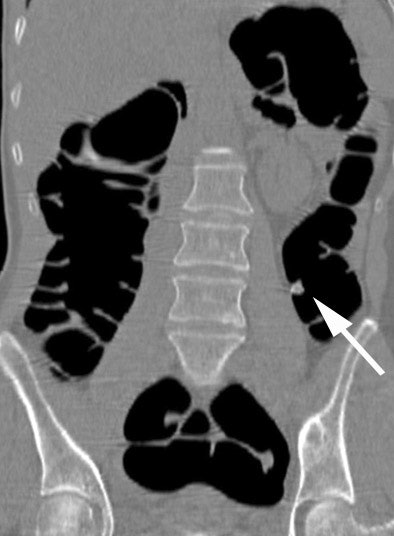

| Axial CT colonographic (VC) image in the prone acquisition shows polyp (arrow) within descending colon. Note homogeneous tagging of the feces throughout the colon. Image courtesy of Dr. Riccardo Iannaccone. |

According to the latest results in 180 patients, conventional colonoscopy identified two carcinomas and 76 polyps in 42 patients; the remaining 138 patients showed no abnormality. Virtual colonoscopy yielded an average per-polyp sensitivity of 48.6% -- 92% for polyps 8 mm or larger.

Average per-patient sensitivity and specificity were 92.8% and 94.2%, respectively. Interobserver agreement was high on a per-polyp basis, and high to excellent on a per-patient basis, Iannaccone said. The estimated effective radiation dose was 1.8 mSv for men and 2.4 mSv females for women, including both supine and prone imaging.